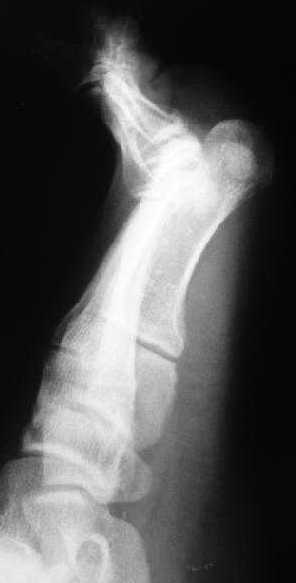

Застарелый вывих I пальца стопы

Пациент 24л. поступил к нам 20.02.08г. для оперативного лечения переломов шейки и диафиза левого бедра из ЦРБ через 1 мес. после травмы.

При поступлении выявлен вывих I пальца левой стопы в сочетании с переломами головок I-IV плюсневых костей.

На сегодня наложен дистракционный аппарат и планируется открытое вправление с пластикой связочного аппарата.